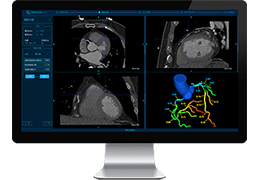

ANYTHINK 经导管主动脉瓣膜置换术分析系统